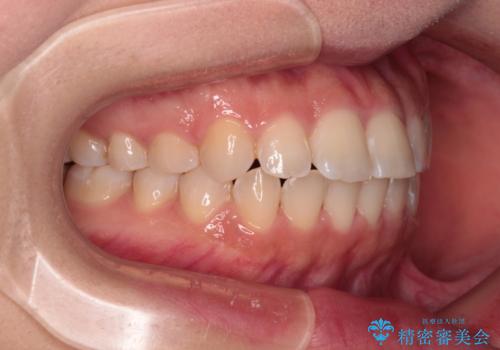

- 前歯のデコボコを気にして来院された患者様です。

マウスピース矯正のような自己管理の煩わしさがなく、早く治療を終えたいとのことで、ワイヤー装置による矯正治療を行うこととしました。

当初予定通り、1年で治療を終えることができました。

後戻り防止はマウスピースで行うため、急に自己管理が必要となるため、移動の最後をマウスピース矯正で行うことで、マウスピース非装着による後戻りリスクを回避する工夫をしています。